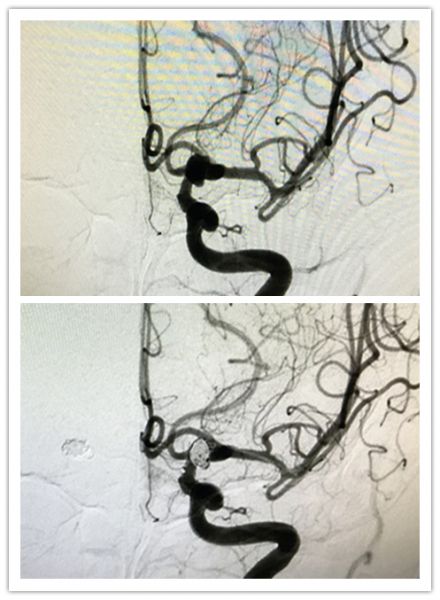

田先生,70岁,因突发剧烈头痛23小时入院。完善CTA提示:蛛网膜下腔出血,颅内双侧大脑中动脉M1段分叉部动脉瘤。神经外科二病区组织讨论后认为:患者颅内双侧大脑中动脉M1段分叉部动脉瘤,动脉瘤宽颈且巨大,行血管内介入治疗需要置入支架辅助,而患者家庭经济困难,治疗费用上无法承受;而开颅手术,患者为双侧动脉瘤,需要双侧开颅的话,手术创伤大,麻醉时间长,对病人机体打击大,手术风险极高,并发症明显。与患者家属多次积极沟通后,家属要求在我院行双侧大脑中动脉瘤开颅夹闭术。通过术前精心准备和研究手术预案,神经外科脑血管病团队决定采取单侧开颅行双侧大脑中动脉瘤夹闭治疗,这种手术方式减少了双侧开颅的创伤,减轻了患者的病痛,手术非常顺利。术后通过医护人员精心治疗和护理,患者恢复良好,未见明显并发症出现。据悉,单侧开颅行双侧大脑中动脉瘤夹闭治疗手术方式目前在省内属于领先地位,在国内能开展此类术式的医院也很少。